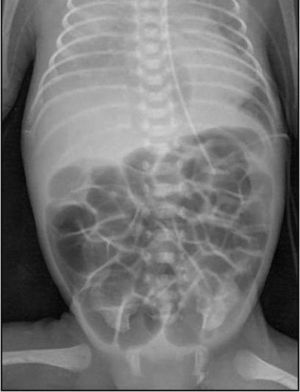

En neonatos, la obstrucción intestinal puede ser diagnosticada mediante una serie de hallazgos radiológicos característicos. La evaluación radiológica es crucial para diferenciar entre las diversas causas de obstrucción intestinal, que pueden ser de origen alto o bajo, y para determinar el manejo adecuado.

1. Radiografía Abdominal: Es la primera línea de imagen utilizada para evaluar la obstrucción intestinal en neonatos. Los hallazgos típicos incluyen dilatación de asas intestinales y la presencia o ausencia de niveles hidroaéreos, lo cual puede indicar si la obstrucción es proximal o distal. Por ejemplo, la «burbuja única» se asocia con atresia esofágica, la «doble burbuja» con atresia duodenal, y la «triple burbuja» con atresia yeyunal.[1-2]

Los hallazgos ecográficos de íleo paralítico en neonatos pueden incluir varios signos característicos. Según la literatura médica, el íleo paralítico se manifiesta por la dilatación de los intestinos, tanto del intestino delgado como del grueso, sin evidencia de obstrucción mecánica.[1] En el contexto de neonatos, especialmente aquellos con encefalopatía hipóxico-isquémica, se ha observado una disminución o ausencia de peristalsis, lo cual es un indicador clave de íleo paralítico.[2] Además, puede haber un aumento de la ecogenicidad de la pared intestinal y la presencia de líquido libre en la cavidad abdominal.[2] Estos hallazgos son consistentes con la falta de movimiento intestinal y la acumulación de contenido intestinal debido a la parálisis del músculo liso intestinal.

Es importante diferenciar el íleo paralítico de la obstrucción mecánica, ya que los hallazgos ecográficos pueden ser similares, pero la ausencia de peristalsis y la dilatación generalizada sin un punto de obstrucción son más indicativos de íleo paralítico.[1] La ecografía puede ser particularmente útil en la evaluación temprana, ya que permite identificar cambios en la peristalsis y la estructura de la pared intestinal antes de que se desarrollen signos radiográficos más clásicos.[1]